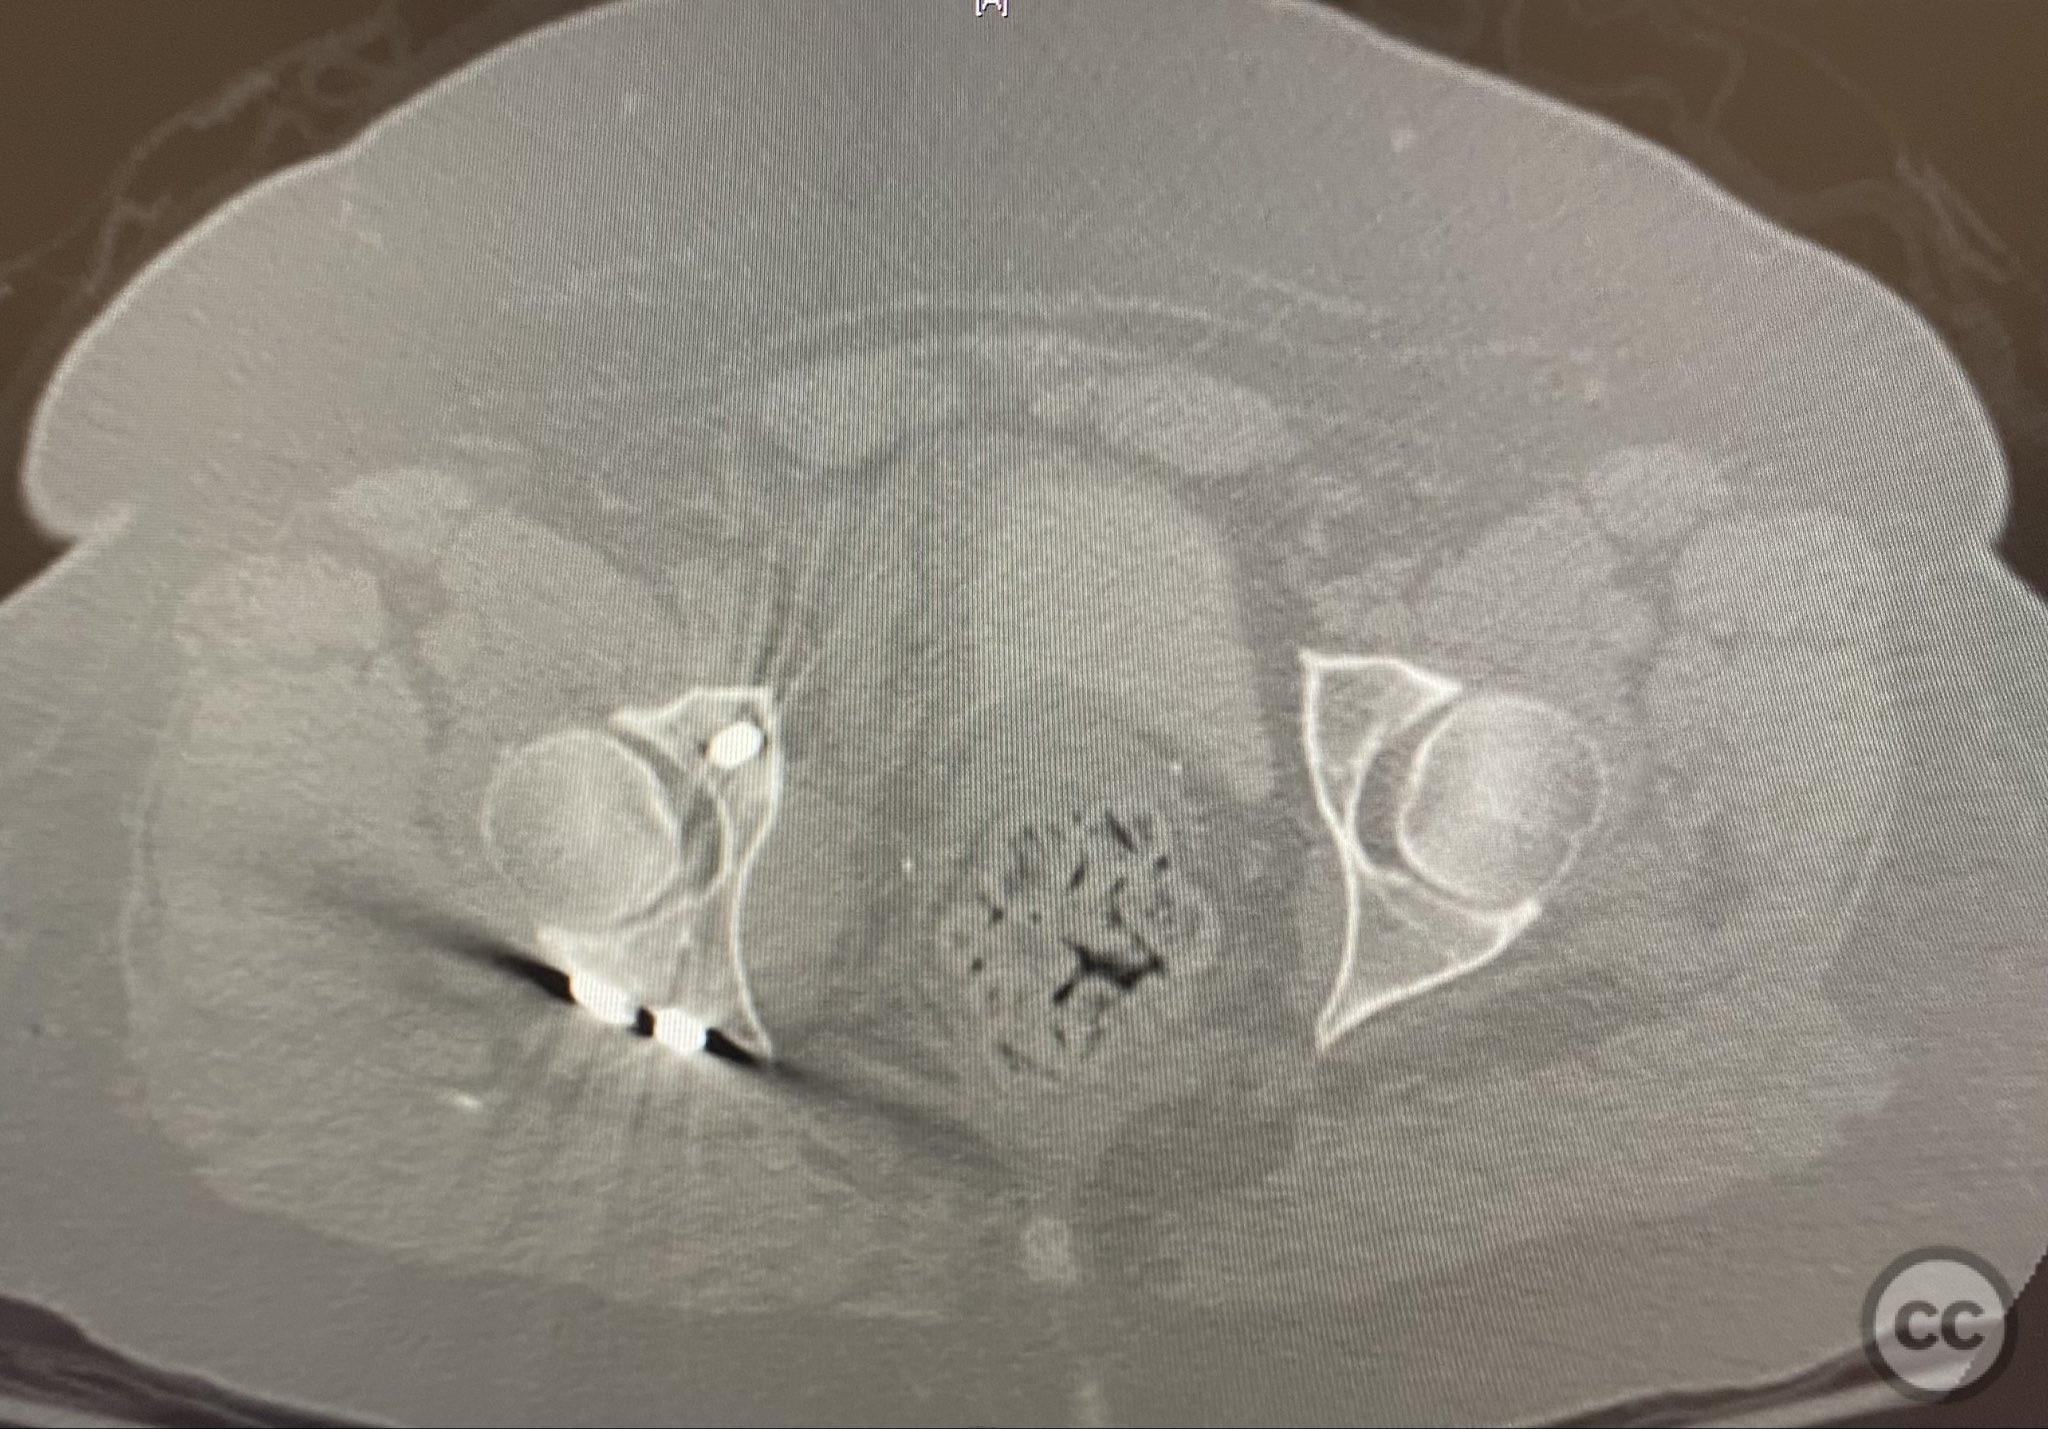

The transverse fracture was manipulated and temporarily stabilized using a reduction clamp applied across the fracture plane. Under biplanar fluoroscopic guidance, a cannulated cancellous lag screw was percutaneously inserted to achieve interfragmentary compression across the transverse component. The reduction clamp was then removed. Posterior wall fragments were anatomically reduced and stabilized with contoured buttress plates spanning both the posterior wall and providing additional stabilization to the transverse component. Postoperative CT confirmed satisfactory reduction and fixation of both acetabular columns and restoration of articular congruity.

Orthopaedic implants used:   Cannulated cancellous lag screw; contoured acetabular buttress plates